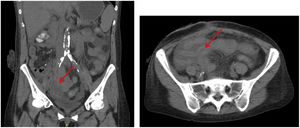

We present the case of a 49-year-old woman with poorly controlled type 1 diabetes and end-stage diabetic nephropathy, who had undergone pancreas-kidney transplantation with enteric drainage in 2010. No complications were reported during the postoperative period or during the biannual follow-up study with Doppler ultrasound. In 2015, chronic dysfunction of both grafts was detected, although imaging tests demonstrated no alterations. In 2020, she presented chronic rejection of the pancreatic graft associated with significant inflammation, destructuring and glandular necrosis, which was managed conservatively. The patient was hospitalized in December 2021 due to an episode of rectal bleeding and syncope. On her arrival at the emergency room, she was hemodynamically stable, with a hemoglobin level of 11.8 g/dL similar to her baseline level. A few hours after admission, she presented rectal bleeding with hemorrhagic shock. Hemodynamic resuscitation was initiated with intensive fluid therapy, and urgent gastroscopy was considered to rule out massive upper gastrointestinal bleeding. However, due to persistent hemodynamic instability despite the initiation of vasoactive drugs, urgent CT angiography was performed, which did not identify the origin of the bleeding but demonstrated notable inflammation of the pancreatic graft in the right iliac fossa. Suspecting a late complication of the pancreatic graft, we performed urgent midline laparotomy and observed a phlegmon involving the pancreatic graft that was also infiltrating the cecum and mesocolic vessels. We conducted an extended right hemicolectomy including the graft, which revealed a bleeding lesion on the anterior side of the right common iliac artery, where the graft was previously located. Ligation and subsequent femoral-femoral bypass were conducted, and hemostasis was achieved. The anatomopathological study of the surgical specimen confirmed the existence of a perforation of necrotic pancreatic tissue towards the right colon as well as the formation of a pseudoaneurysm and aortoenteric fistula. After surgery, the patient progressed favorably and was discharged without recurrences (Image 1).

Classically, pancreas transplantation has been deemed to have a higher complication rate than other solid organ transplants4. The most frequent complications are graft thrombosis, followed by acute pancreatitis, acute and chronic rejection, and the formation of pancreatic fistula5. Arterioenteric fistulae are the incidental communication of a blood vessel and the intestine. They can present as chronic anemia, upper or lower gastrointestinal bleeding, or hemorrhagic shock6. Pancreatic grafts are especially susceptible to this complication due to chronic enzymatic damage by the pancreatic fluid over the anastomosis. This, added to the existence of risk factors such as intestinal drainage of the pancreatic graft instead of towards the urinary bladder (like our patient), perioperative infections or the existence of arteriovenous malformations, result in the formation of fistulae that communicate arteries of the pancreatic graft with the gastrointestinal tract4.

For diagnosis, initial clinical suspicion is essential7. Gastrointestinal endoscopies can be useful to rule out other causes of bleeding, although they are limited in the case of hemodynamic instability or heavy bleeding that prevents visualization8. CT angiography is able to detect extravasation of contrast material into the intestinal lumen, although this requires a high volume of bleeding, which is not always observed. Arteriography makes it possible to detect the exact point of bleeding to carry out definitive treatment by embolization and/or surgery5. Therefore, gastrointestinal bleeding secondary to arterioenteric fistula formation in the context of pancreatic transplantation is a low-frequency complication associated with high mortality that is complex to diagnose and treat. Therefore, prevention is essential, and a systematic radiological follow-up should be considered in patients with established risk factors.